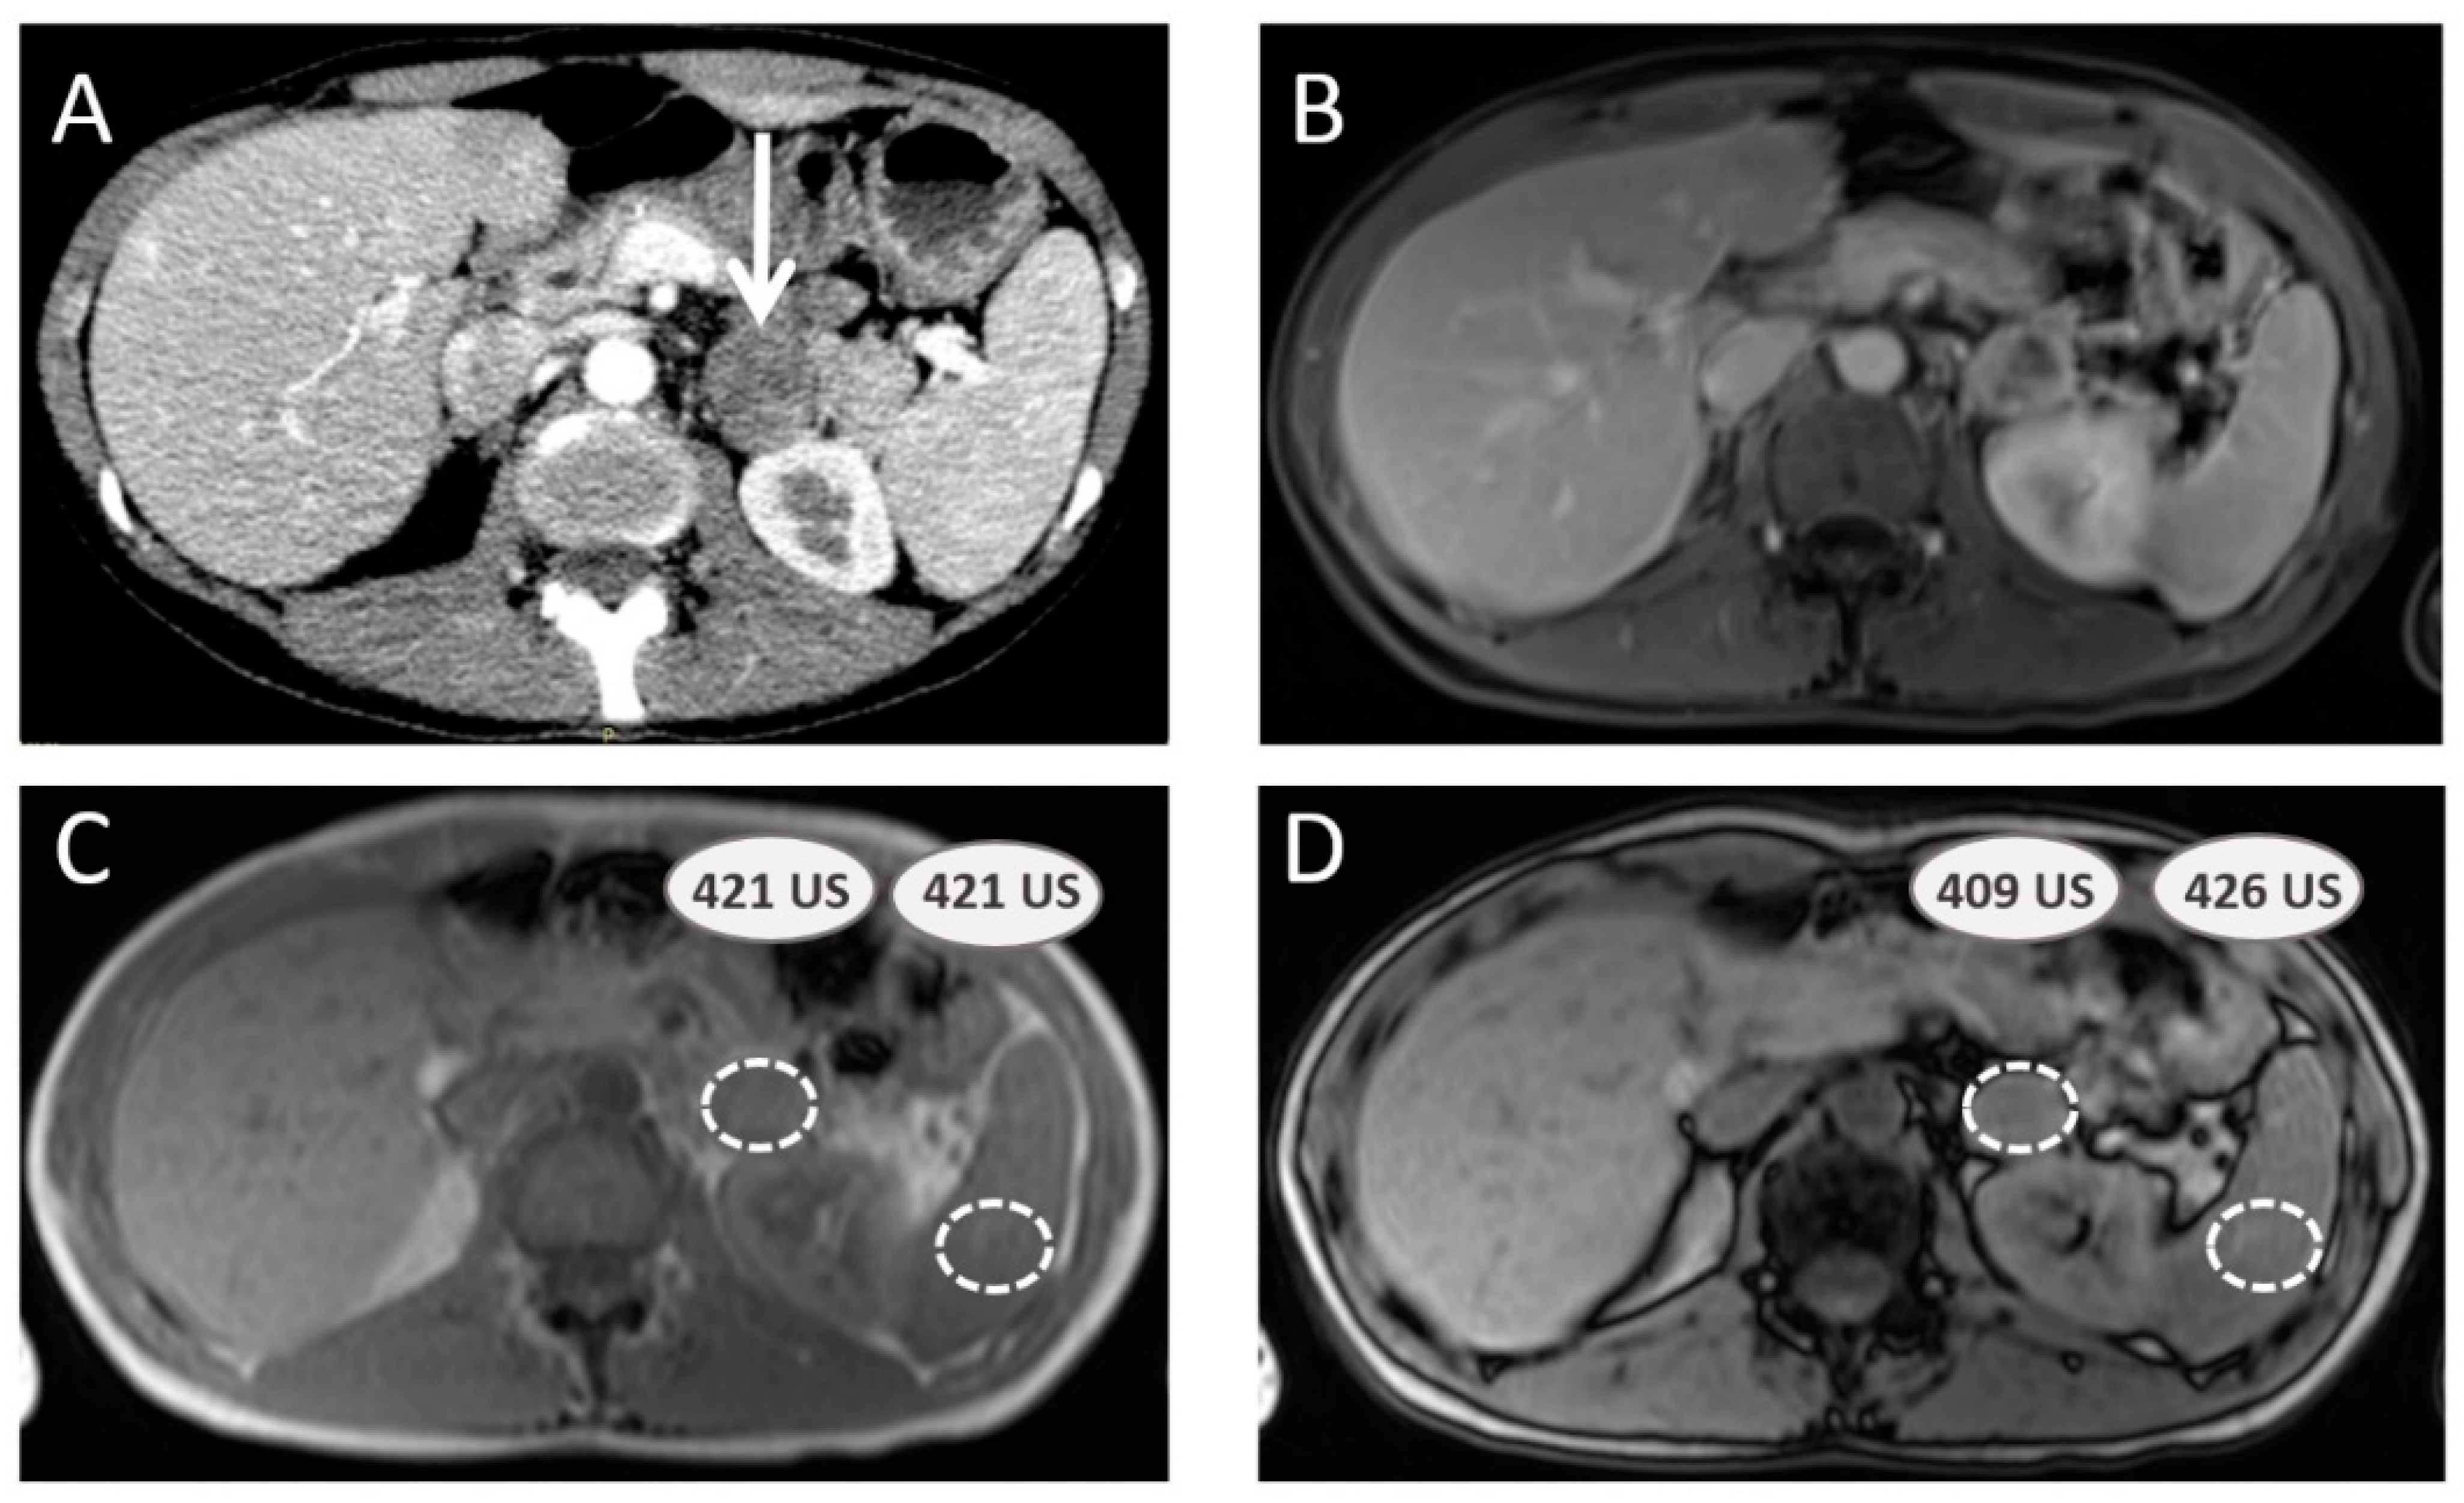

3.3. Additional Value of Magnetic Resonance Imaging with Chemical Shift Imaging

3.4. Pheochromocytomas and Paragangliomas: Variable Morphological Characteristics Using Anatomical Imaging